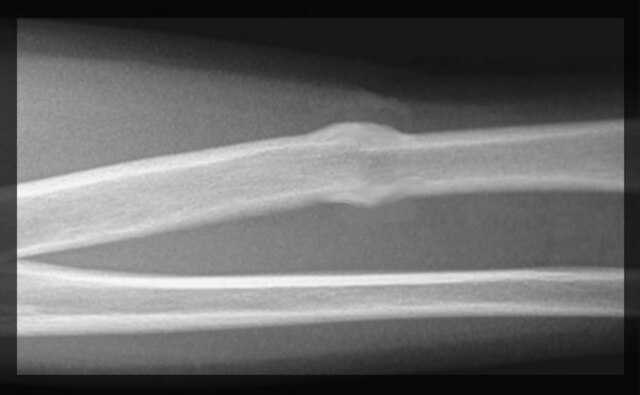

Der Kallus – Synonyme sind „Knochenkallus“, „Frakturkallus“, „Bruchkallus“ – wird von den Osteoblasten aufgebaut. Die Neubildung an Knochensubstanz ist unter bestimmten Voraussetzungen nach einigen Wochen mit Hilfe von Röntgenaufnahmen sichtbar. Eine Voraussetzung für die radiologisch sichtbare Kallusbildung ist, dass die Bruchenden nicht hundertprozentig aufeinanderstehen bzw. passen oder Bewegung haben, so dass also ein Spalt überbaut werden muss. Diese Form der Knochenbruchheilung wird Sekundärheilung, auch indirekte Frakturheilung genannt.

In solchen Fällen bauen die Osteoblasten während der Heilungsphase eines Knochenbruches eine radiologisch deutlich sichtbare Verdickung um die Bruchstelle. Die Verdickung wird in einem lange dauernden Prozess (über Monate bis Jahre) von den Osteoklasten meist wieder auf die normale Knochendicke abgebaut. Kommt es zu einer Kallusbildung zwischen nah beieinanderliegenden Knochen wie Elle und Speiche oder Schien- und Wadenbein, kann das überschießendes Knochengewebe auch die bindegewebigen Verbindungen dieser Knochen (Membrana interossea) einschließen und zwischen ihnen eine Synostose verursachen. Man spricht dann von einem Brückenkallus.